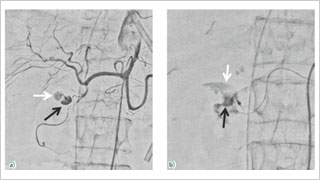

Trinias在脑动脉瘤弹簧圈栓塞术中的性能

德洲会 名古屋德洲会综合医院 脑神经外科

天野 贵之